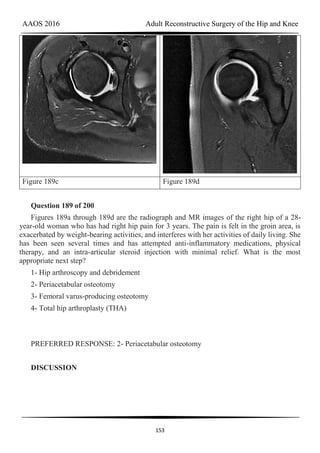

AAOS 2016 Adult Reconstructive Surgery of the Hip and Knee

134

to be well fixed, and, as a result, should be retained in this older patient. An evaluation of

stability could lead to possible revision of the acetabulum, and implants should be available.

Question 164 of 200

A 75-year-old woman has a 1-year history of right hip pain and a right total hip arthroplasty

(THA) performed in 1999. Her left THA, performed in 2002, is asymptomatic. Plain

radiographs show that all of the components appear well fixed and in good position. There is

evidence of eccentric polyethylene wear of the right hip with focal osteolysis of the calcar and

great trochanter (with none of these findings on the left hip). What is the most likely

explanation for her right hip pain?

1- Acute periprosthetic infection